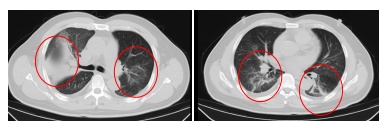

发热门诊医生详细询问顾先生的既往病史,并为其进行细致的体格检查。胸部CT结果显示,顾先生的双肺存在大面积的炎症病变。

在感染科医护团队的精心治疗与细致护理下,顾先生的发热、咳嗽、胸闷等症状逐渐缓解。复查的CT结果显示,肺部炎症情况得到了明显的改善。目前,顾先生已经顺利康复出院。